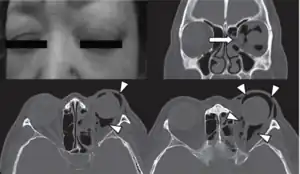

![]() | |

| Woman with preorbital swelling in orbital emphysema shown in CT scans | |